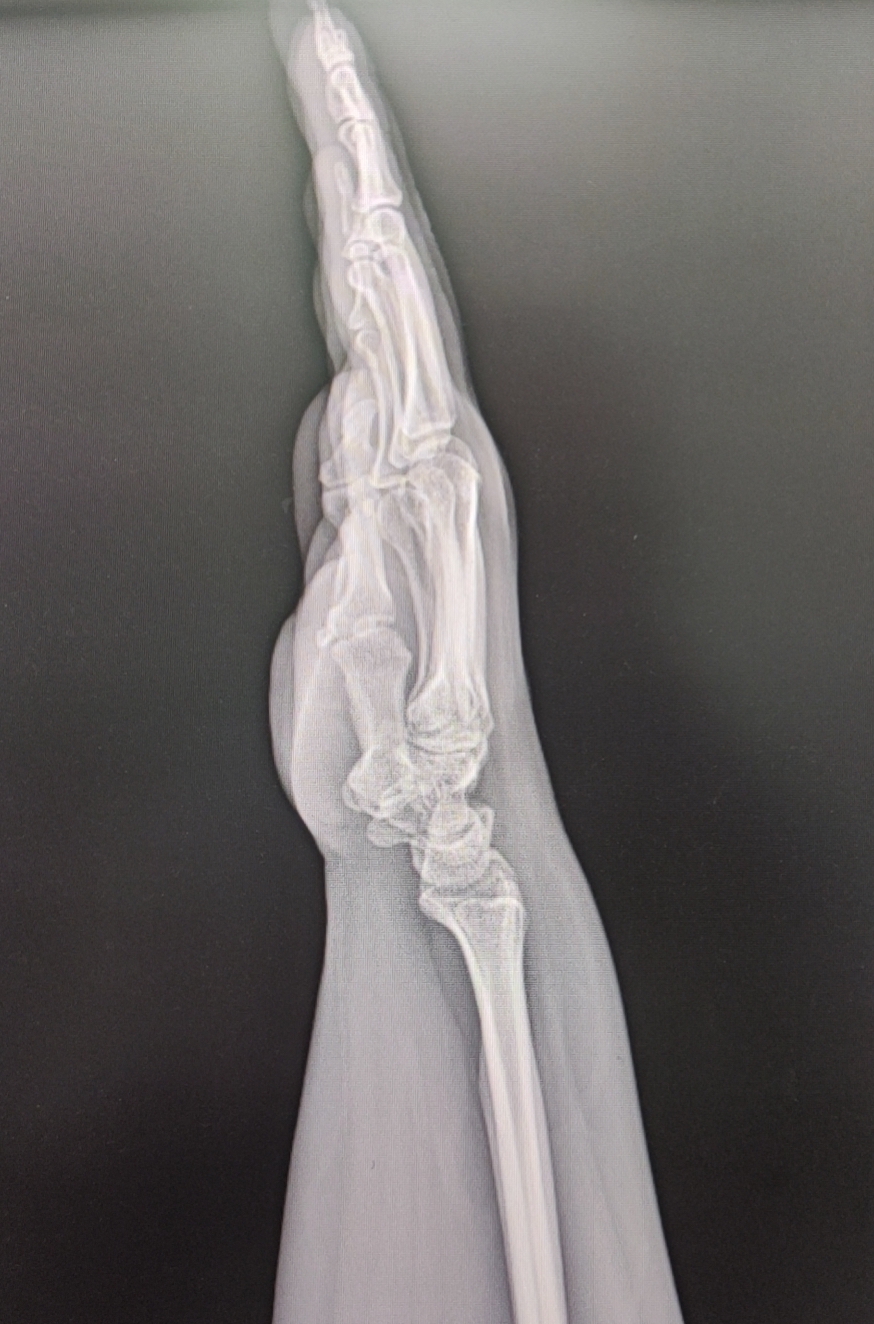

【影像】腕关节正位片见腕部骨质未见异常,尺骨正变异(-)。